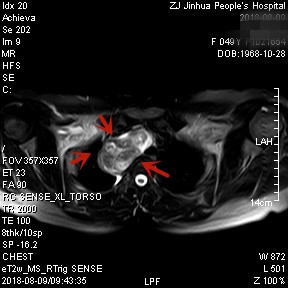

上图均示MRI下的肿瘤情况,红色箭头示肿块

上图示颈部与胸内的病灶关系密切,但绿色箭头处似有分界,仅少许相连